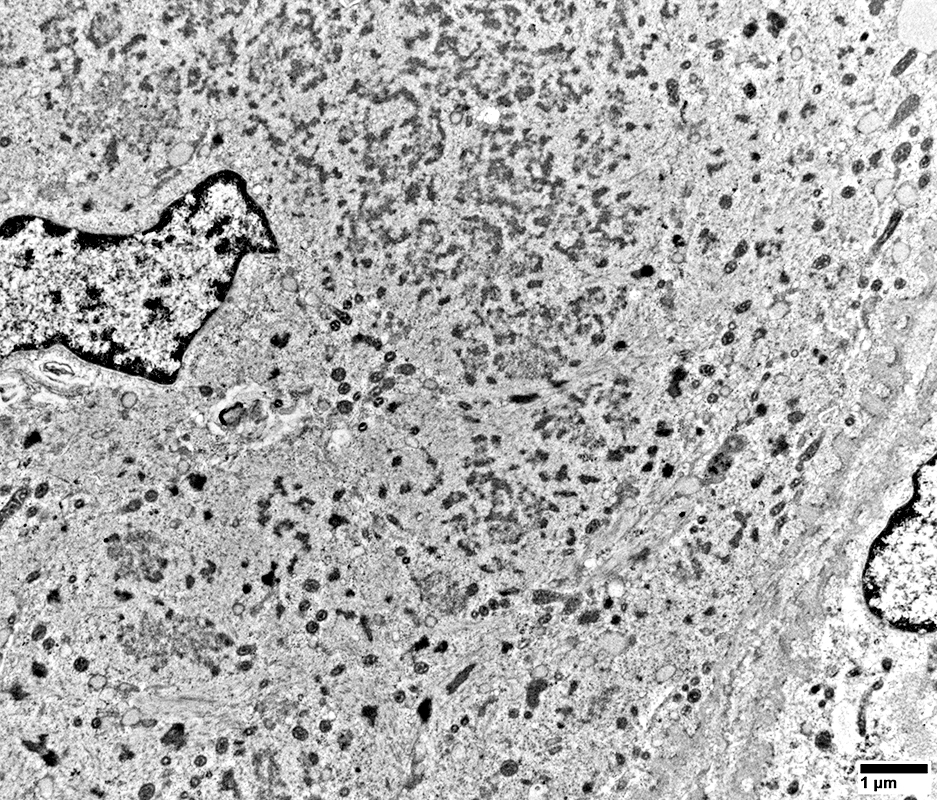

DM-VP Ultrastructure: Abnormal Mitochondria

From: R Schmidt

DM-VP

Abnormal Mitochondria

Sizes: Generally small

Cristae: Dense

Shapes: Some elongated

No filamentous inclusions

Muscle fiber morphology

Sarcomere structure is missing or abnormal

Mitochondria

Many are Small & Round (Arrow, Below)

Sarcoplamic Aggregates (Below)

Small, Irregularly shaped, Amorpohous